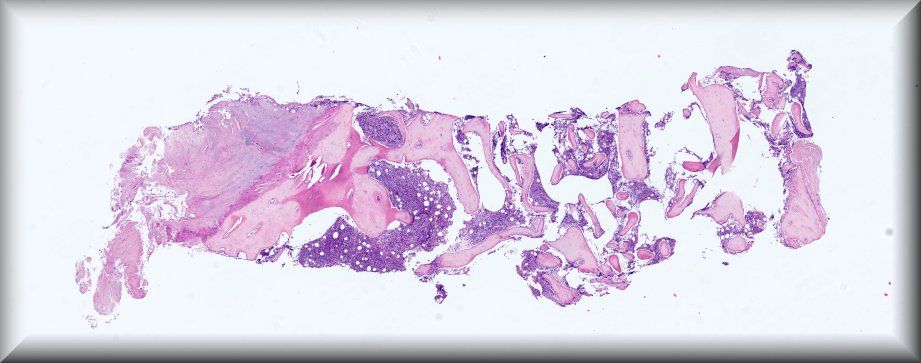

Caso 4.- Paula Tenhaeff Lackschewitz, Gerónimo Llopis, Raquel Martínez Marcos, Esther Roselló Sastre.

Hospital General Universitario de Valencia.

Varón de 28 años, con antecedente de infección por VIH diagnosticada en 2019 y abandonodel tratamiento antirretroviral. Consulta por un mes de evolución de lesiones cutáneas pápulo-nodulares eritematosas y descamativas, tos seca, pérdida ponderal de 10 kg y edemas enextremidades inferiores. En la exploración presenta fiebre de 39 °C, taquicardia y hepatoesplenomegalia. La analítica muestra pancitopenia severa, hipoalbuminemia,hipertransaminasemia y ferritina >90 000 µg/L. Serologías para VHB, VHC, CMV, VEB yBartonella negativas, con beta-D-glucano positivo. Con sospecha de leismaniasis/linfoma serealiza biopsia de médula ósea.